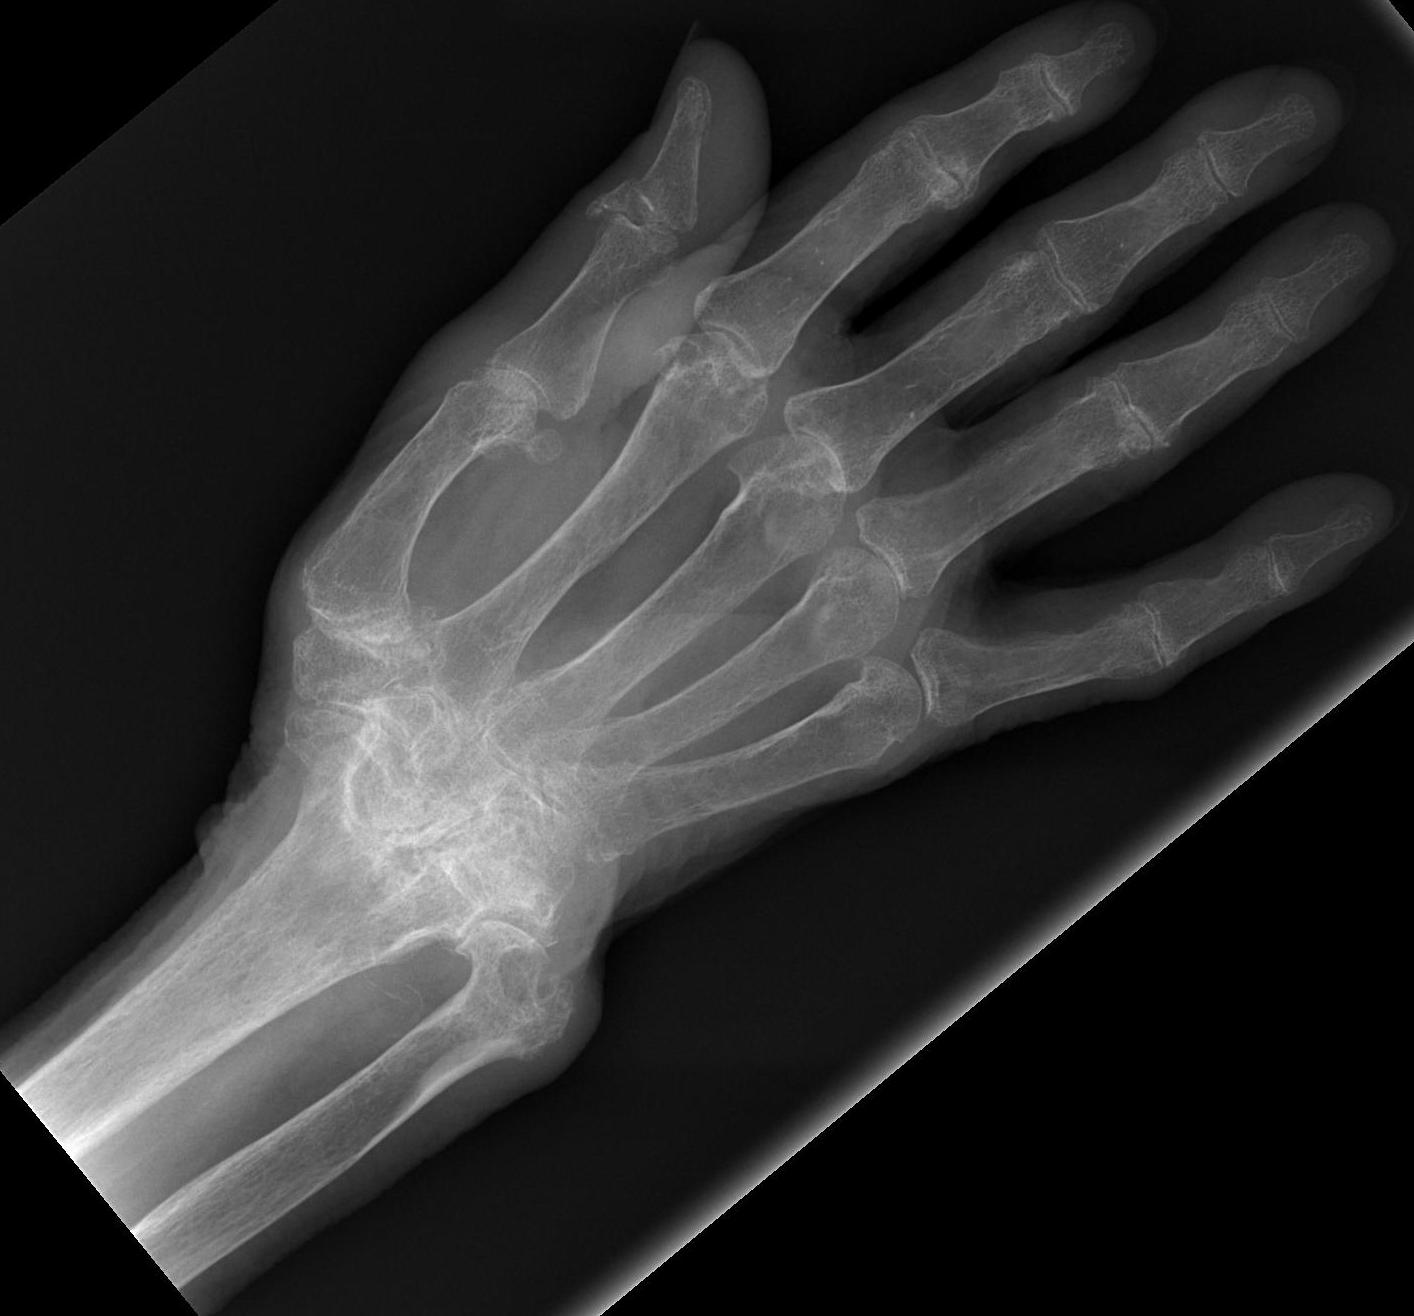

Hemophilia

Hereditary bleeding disorder due to defective and/or deficient factor VIII molecule

Haemophilia A

FVIII deficiency